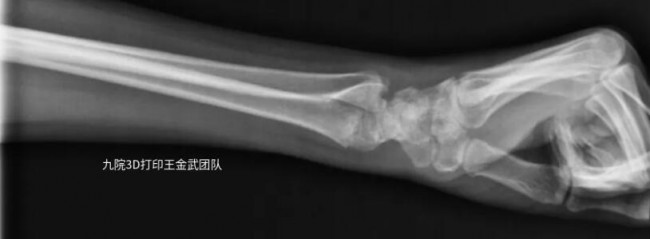

近日,上海第九人民医院王金武教授团队分享了通过3D打印外固定支具助力患者腕关节骨折恢复的案例。

患者左臂桡骨远端骨折,骨折固定后佩戴3D打印固定支具辅助恢复情况良好。